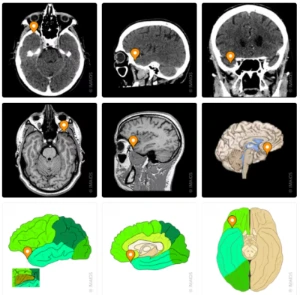

아는 얼굴에 바로 반응하는 측두극 (temporal pole)

그런데 새삼 이 개념을 다시 소환할 결과가

수집되었다. 십수 년 만에 다시 만나도, 특히

유명한 사람 얼굴은 일부만 봐도 우린 누군지

안다. 또 목소리만 듣고도 바로 누군지 안다.

하지만 뇌 어딘가에 문제가 생기면 이 능력이

사라져 곤란을 겪기도 한다. 2021년 원숭이

두뇌의 측두엽 앞쪽 끝, 시각 피질에 해당하는

측두극(temporal pole)에서 특정 얼굴을 보고

바로 기억과 ‘연결’시키는 자리가 확인되었다.

그러니까 소설가 로스가 명명한 할머니 세포는,

한 개의 할머니 뉴런이 아니라, 카나리아가

사투리를 배울 때 새로 ‘연결된’ 일련의

신경회로들과 유사한 방식이라고 예상된다.